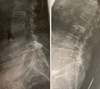

Varon joven con dificultad para la marcha y flexión del tronco. Pérdida de fuerza en el pie

Espondilolistesis istmica de L5-S1

Indicación qx fx toracolumbares

Clínica neurológica progresiva Fragmentos óseos canal medular Cifosis angular >25 grados Pérdida >50% altura vertebral

tto fx osteoporóticas

Cifoplastia ( balón que recupera altura vertebraly introduce cemento en cavidad) Vertebroplástia ( CI fx estallido )